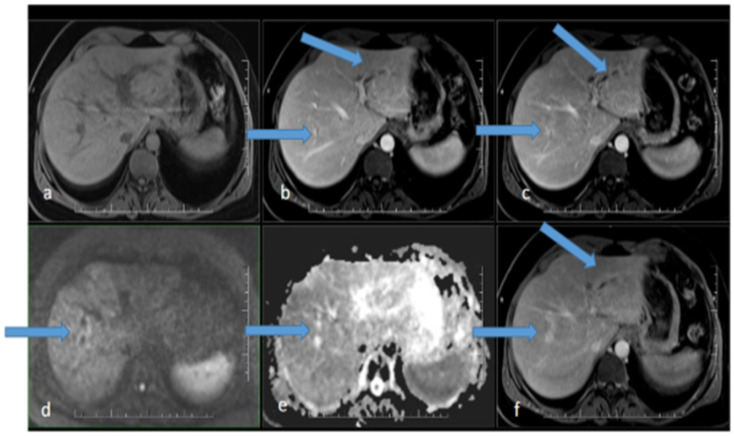

Case presentation: We report a case of early syphilis in the secondary stage, manifesting as sclerosing-cholangitis-like changes shown on ultrasonography, MR, and CT. Narrow-spectrum antibiotic therapy with procaine benzylpenicillin led to a consistent decrease in and normalization of levels of serum bilirubin and other markers of hepatic injury. Repeated sonography and MR cholangiography showed minimal residual changes in the intrahepatic biliary tree.